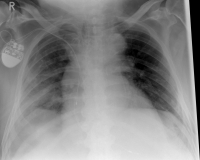

Pneumothorax / tension pneumothorax

In some cases, the sharp rib fragments cause lung or outer chest wall injuries. As a result, air can enter the gap between the lung and chest wall and cause a so-called pneumothorax, which must be treated by drainage.

In rare cases, a so-called tension pneumothorax may develop, which under certain circumstances can also be life-threatening. Due to an injury-related valve mechanism, air from the lungs flows into the gap between the lungs and the chest wall, but can not escape. As a result, the organs are shifted in the chest and concentrated, so that the circulatory function is impaired. It requires, in these cases, an immediate delimbing in the hospital or by an emergency physician.

Hemothorax

If blood accumulates in the gap between the lungs and the chest wall due to the injury of a blood vessel or the lungs, this is called hematothorax. If there is still air in the gap, it is a hematopneumothorax. Both the hematopoietic and the hematopneumothorax must often be treated with a drainage.